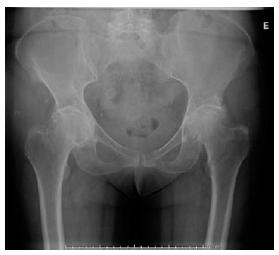

A admissão no serviço de Ortopedia do Centro Hospitalar ocorreu a 19/11/2020, com o diagnóstico de coxartrose esquerda, para cirurgia eletiva, que só se viria a realizar a 21/11/2020. Em relação aos exames pré-operatórios, foram realizadas análises sanguíneas, que se encontravam dentro dos valores de referência; eletrocardiograma, com ritmo sinusal; e radiografia do tórax e bacia (Figura 1). A senhora foi também submetida a uma avaliação por parte do anestesista, obtendo um risco cirúrgico de ASA II (American Society of Anestesiology), indicativo de doença sistémica leve. No dia 21/11/2020, foi submetida a artroplastia total da anca esquerda, sob raquianestesia, tendo o pós-operatório decorrido sem intercorrências e com controlo radiográfico da bacia após a cirurgia (Figura 2).